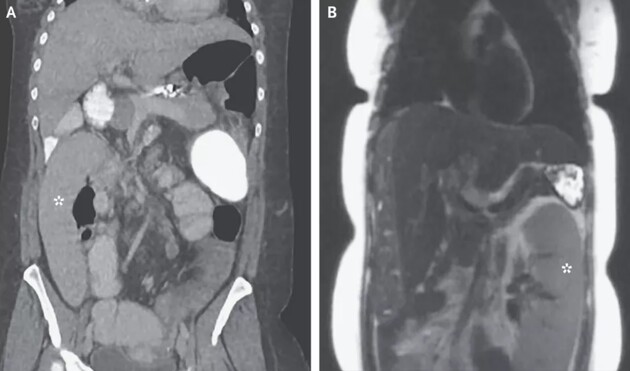

Але у 36-річної жінки, яка звернулася за допомогою, медики знайшли селезінку в правому нижньому кутку живота. Цікаво, що всього за два дні до звернення до відділення швидкої, жінка проходила дослідження на рак печінки. Тоді медики зробили знімок її живота, але не виявили жодних відхилень. Але вже через день жінка почала відчувати біль і блювоту.

У відділенні швидкої лікарі знову зробили знімки живота пацієнтки і з'ясували, що її селезінка змістилася в протилежну сторону. Біохімічний аналіз показав підвищений рівень ферменту підшлункової залози ліпази (більш ніж в 10 разів).